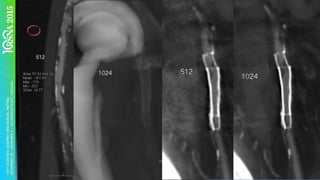

§  Recon	larger	matrix	–	1024x1024

1024	Matrix

Examples